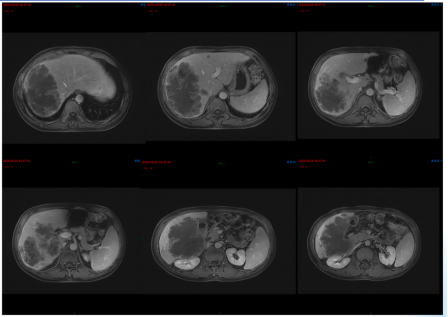

影像学检查:2024年7月30日,院外腹部CT显示乙状结肠管壁增厚,考虑肿瘤性病变(cT3N2,图1),2024年8月5日,肝脏MRI显示肝脏多发转移灶(侵犯门静脉右支、肝右静脉,图2)。2024年8月2日胸部CT显示双肺结节待排(图3)。

目前诊断:乙状结肠腺癌伴肝转移(cT3N2M1a IVA期) NRAS p.Q61L突变,TMB 6.2,MSS;中度贫血;双肺多发结节,转移待排(图7)。

目前诊断:乙状结肠腺癌伴肝转移;肝动脉内钇90放射治疗后;中度贫血;双肺多发结节,转移待排(图12)。

CEA、CA19-9略微升高(图17),肝脏多发转移瘤较前增多、增大(图15/16),双肺结节较前增多、增大(图14),评估为PD。

图14. 2025年2月25日CT:双肺结节,较2024年12月27日CT增多、增大